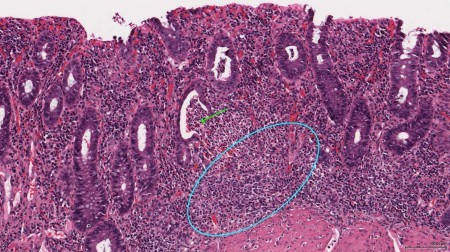

Диагноз «атрофический колит» гастроэнтерологи выставят в случае, если воспаление слизистой оболочки толстого кишечника спровоцировал истончение последней. Такие изменения возникают в случае запущенного острого колита, его хронизации (перехода в хроническую форму) и прогрессированию в язвенную, а затем уже и в атрофическую форму.

Когда в процесс втягивается мышечный компонент кишечника – это свидетельства процесса, известного как диффузный атрофический колит. Сила и амплитуда перистальтических волн кишечника падают, ободочная кишка сужается, что приводит к уменьшению ее внутреннего просвета и снижение функций органа.

Врачам, для постановки диагноза «атрофический колит» и для того, чтобы лечение было максимально эффективным, помимо общих и биохимических анализов крови, мочи и кала, наиболее эффективными методами диагностики будут инструментальные методы:

- УЗИ органов брюшной полости (визуализируется истончение стенки ободочной кишки с одновременным сужением ее просвета);

- эндоскопическая колоноскопия (с помощью колоноскопа, снабженного видеокамерой, специалисты могут осмотреть непосредственно состояние слизистой оболочки всего толстого кишечника);